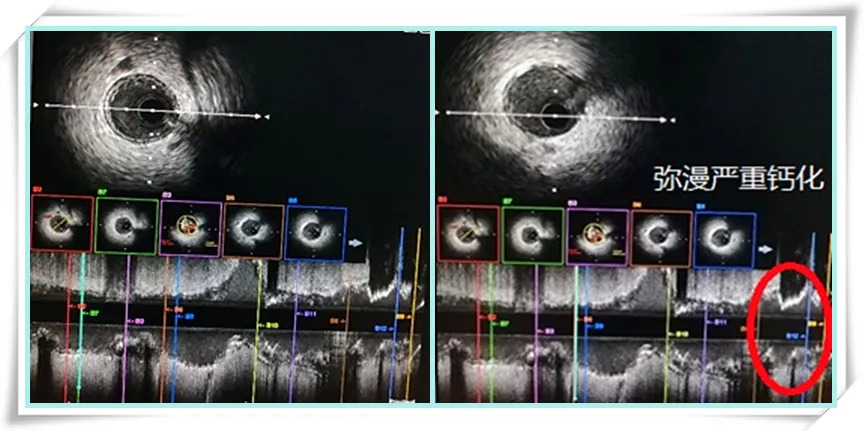

2019年07月19日,我院心内科团队采用先进的影像技术,为严重肾功能不全患者成功施行“零造影剂”支架植入术。该患者为65岁女性,肾小球滤过率12ml/min,反复发作心绞痛,多种药物治疗仍不能有效减少心绞痛发作,病人迫切需要介入治疗,但是患者肾脏情况又不允许使用造影剂,所以决定采用血管内超声指导冠脉介入治疗。手术团队术中准确判断冠脉开口,建立手术通路,成功输送IVUS超声导管依次进入各冠脉血管。通过IVUS确定罪犯血管为右冠状动脉,病变部位为右冠开口至中远段弥漫病变,狭窄80%以上,病变性质复杂,近段血管有270度以上不连续的深、浅层钙化,再次增加了手术难度。经IVUS准确测量病变长度和血管直径后,分析IVUS影像结果,综合考虑病变情况制定手术策略,精准地于右冠脉植入2枚支架,顺利完成手术。术后患者症状显著缓解,3天后出院。

IVUS扫描:判断病变性质、测量血管直径、病变长度